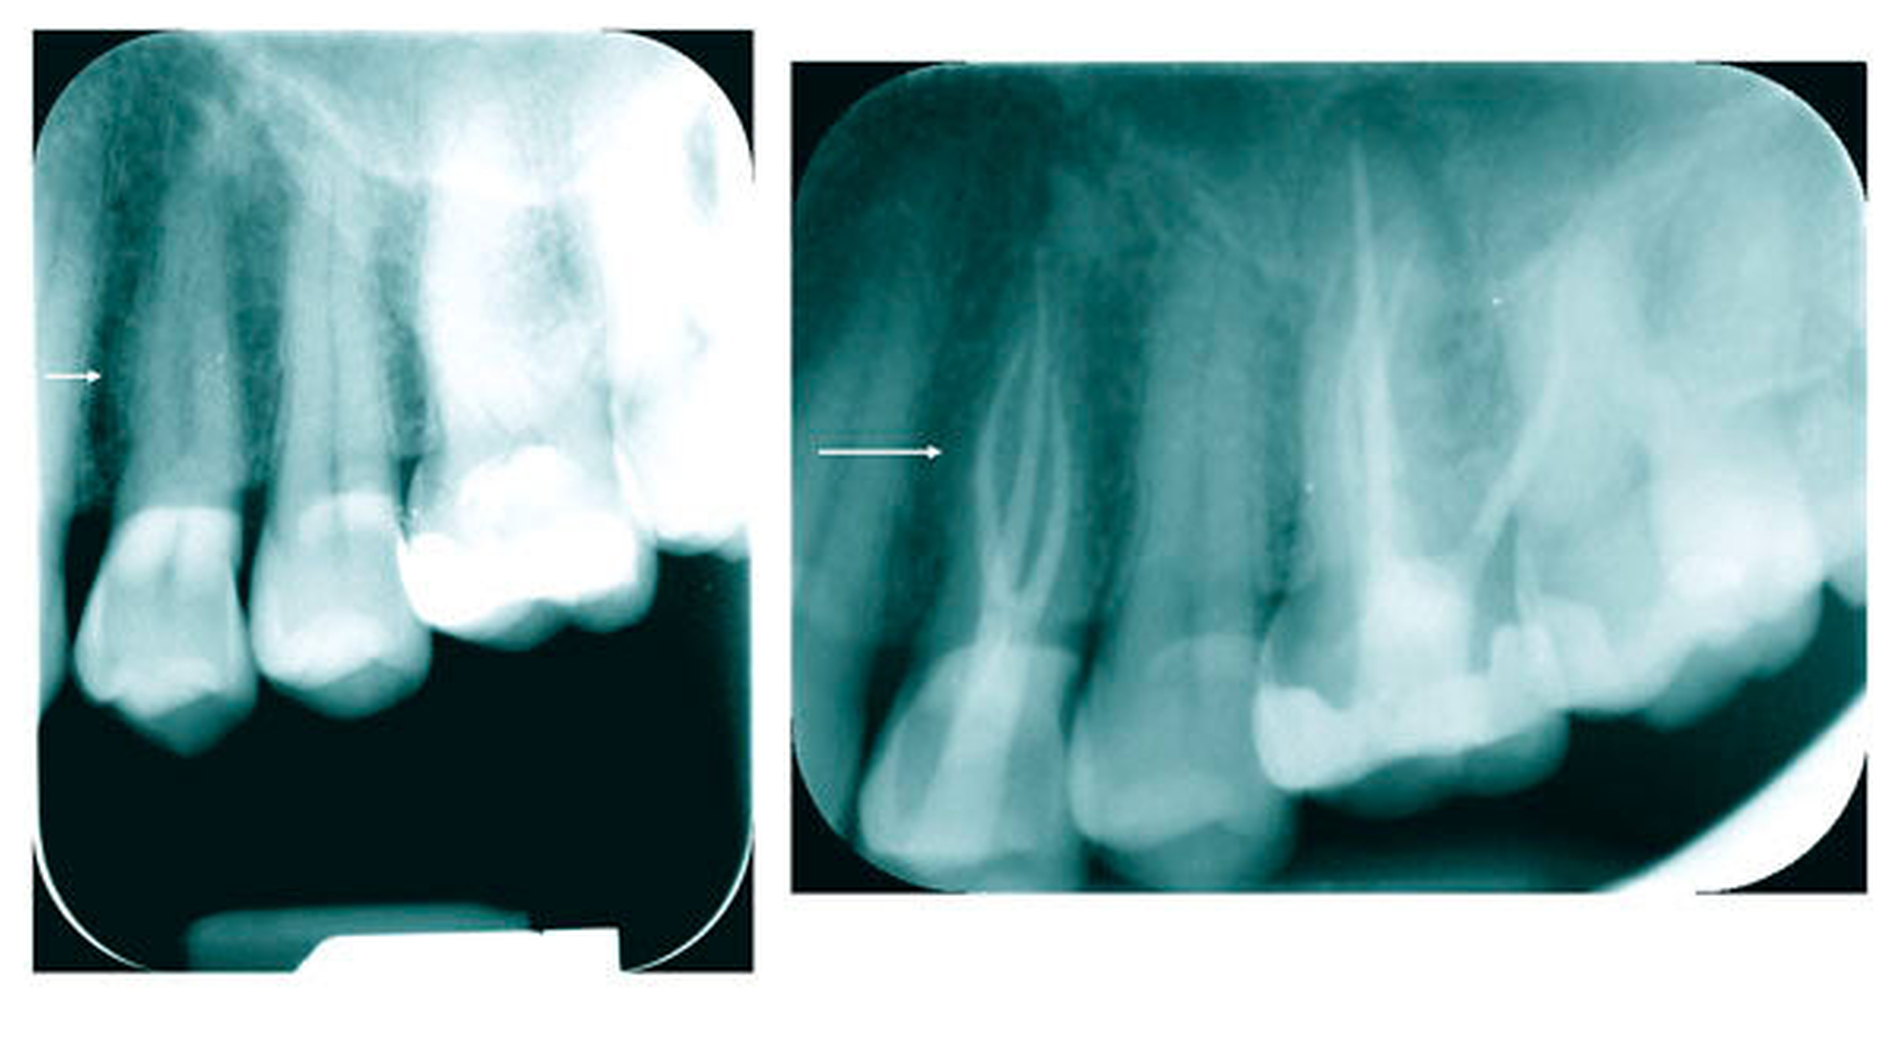

Beide Prämolaren können drei Kanalsysteme mit drei Wurzeln oder drei Kanalsysteme mit zwei beziehungsweise mit einer Wurzel aufweisen (Abbildung 7). Das Auftreten dieser Kanalkonfigurationen wird in der Literatur mit 1 bis 2 Prozent beschrieben [Sert und Bayirli, 2004].

Drei mögliche Hinweise können bei der Diagnostik eines dreikanaligen Prämolaren hilfreich sein. Der erste Hinweis ist eine nicht klar abzugrenzende Wurzelkontur in der diagnostischen Röntgenaufnahme. Dreikanalige obere Prämolaren zeigen im klassischen Röntgenbild im koronalen bis mittleren Wurzeldrittel eine oft bauchige Struktur. Diese korrespondiert in der Regel mit der Stelle apikal der Aufteilung in zwei bukkale Kanäle (Abbildung 8). Klinisch kann dann in den meisten Fällen bei Sondierung bukkal eine deutliche Einziehung unterhalb der Schmelz-Zement-Grenze mit der Sonde ertastet werden, dies ist der zweite Hinweis (Abbildung 9). Der dritte Hinweis zeigt sich nach Trepanation und Darstellung des Kavumbodens und des vermeintlichen bukkalen Kanaleingangs. Dieser wird häufig nach hinreichender Darstellung in mesiodistaler Richtung oval und gibt dann die Sicht auf die beiden eigentlichen Kanäle frei (Abbildungen 10 und 11).